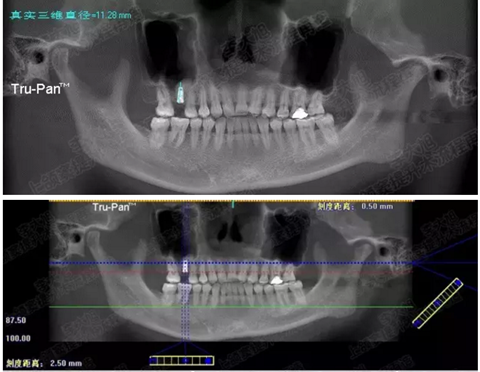

病例五

剩余不足1mm

112.png

提升10mm

113.png